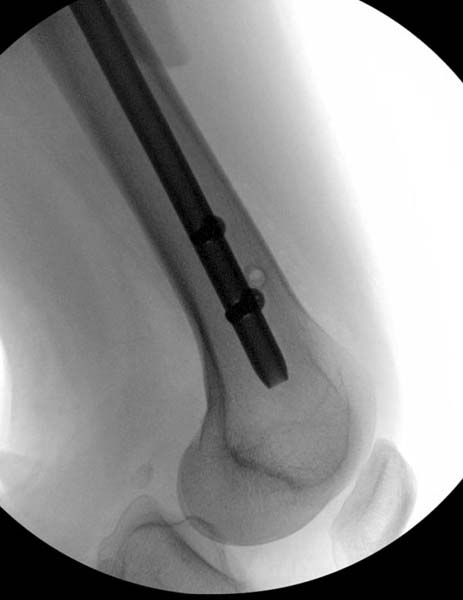

Около 11.00 вечера больная переведена в реанимацию, без сознания, но стабильная.. На третьий день провели стабилизацию перелома бедра антеградным остеосинтезом.

Закрытый БИОС решает множественные проблемы связанные с лечением переломов, но проблема дистальной блокировки без рентгена до сих пор остается нерешенной. Рекламированные производителями приспособления для дистальной блокировки из-за различной кривизны кости не эффективны или стоит очень дорого (Smith&Nephew SureLock). Задержка операции из-за блокировки не всегда удовлетворяет, и многих вынуждает искать альтернативные методы фиксации. С результатами таких действий, остеомиелитом и несращениями, встречаемся в ежедневной жизни..

Для решения проблемы дистальной блокировки компания DigiMed недавно предложила систему блокировки без рентгена. Пока в стране только два набора и только для антеградных гвоздей, но компания работает над созданием устроиства для других гвоздей тоже..

Результат первых случаев показала отсутствие разницы между занятиями на муляжах, а также Workshop и с удивительной точностью вывел латерально над кожей специальное сверло. Дальше по сверлу тонкий направитель и проводится сверление каннюлированным сверлом....